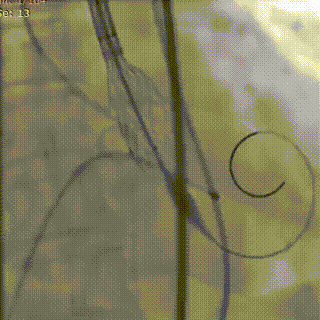

第一次瓣膜释放

可回收功能重新调整瓣膜位置

手术过程(三):第二次释放时,瓣膜植入深度在0-2 mm,快速起搏后缓慢释放瓣膜,顺利完成释放。释放完成后,行DSA评估瓣膜释放情况,可见反流量明显减少。超声结果显示即可跨瓣压差几乎为零。

第二次瓣膜释放

释放完成效果